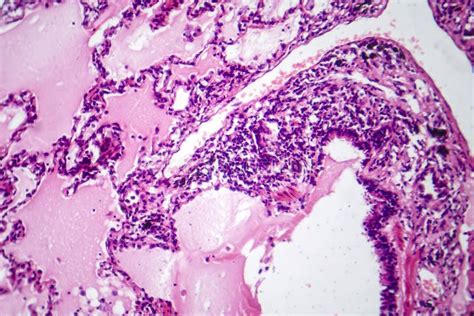

So, how is adenocarcinoma diagnosed ? Well, it usually starts with a physical exam and a review of your medical history. Your doctor will ask about your symptoms, risk factors, and family history of cancer. Depending on your symptoms and the suspected location of the cancer, they may order a variety of tests, such as imaging scans (like X-rays, CT scans, MRI scans, and PET scans), blood tests, and biopsies. A biopsy is the only way to definitively diagnose adenocarcinoma. During a biopsy, a small sample of tissue is removed and examined under a microscope to look for cancer cells. The type of biopsy will depend on the location of the suspected cancer.